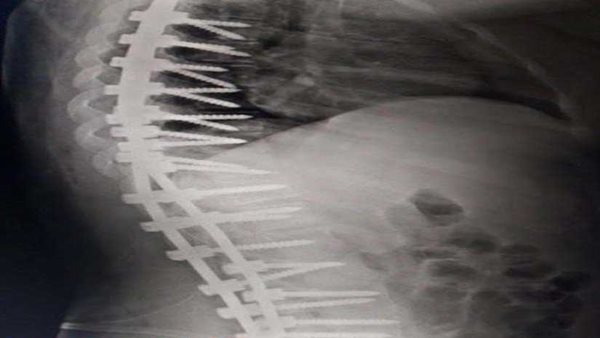

نجح فريق طبي بمستشفى الملك عبد الله بن عبد العزيز بمحافظة "بيشة" السعودية في إنهاء معاناة فتاة من تحدب وانحناء العمود الفقري.

وقالت وكالة الأنباء السعودية "واس": إن الفريق الطبي المعالج للفتاة قرر- بعد إجراء الفحوصات الطبية- خضوع المريضة لعملية جراحية جرى خلالها تعديل الفقرات الصدرية والقطنية وتثبيتها، تكللت العملية بالنجاح وتحسنت الحالة الصحية للمريضة، بعد شفائها من التحدب والانحناء.